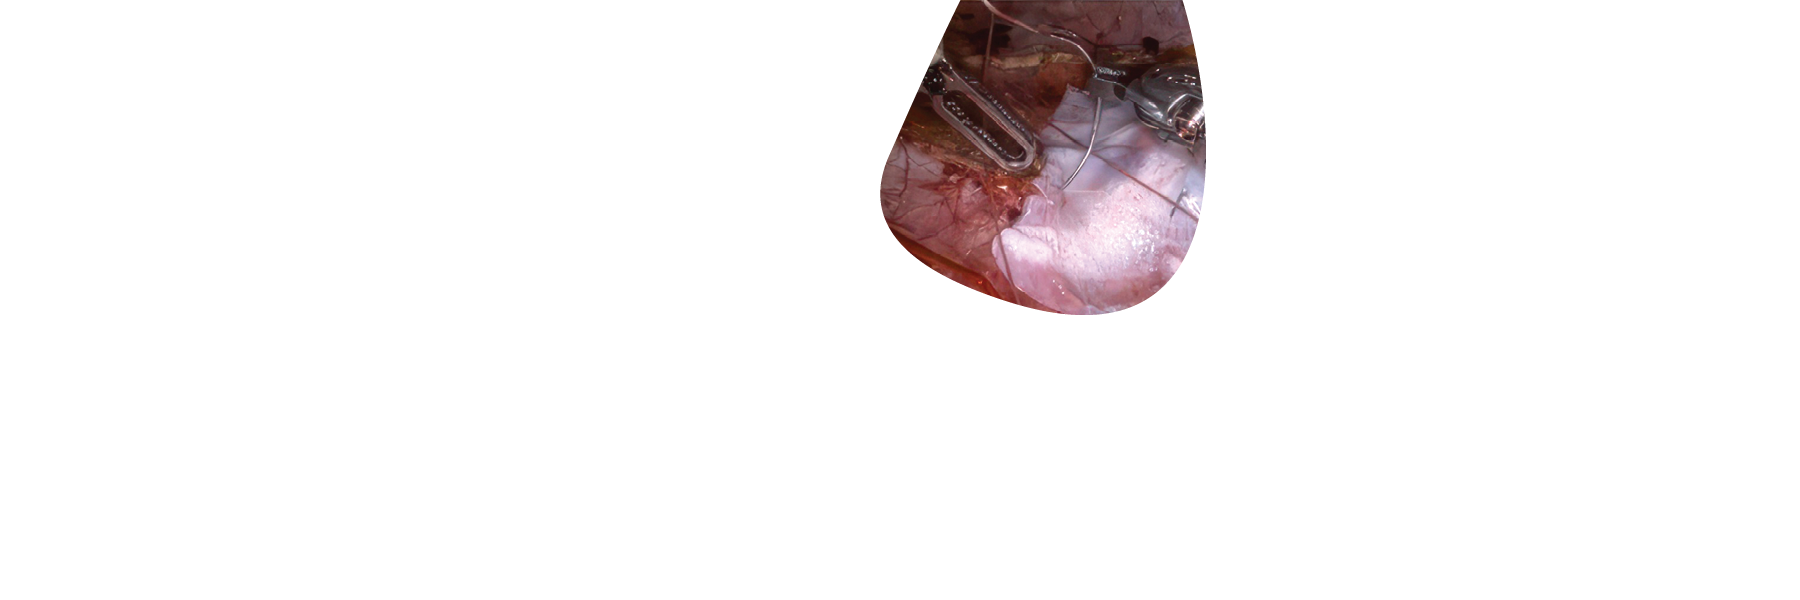

STRAVIX◊ Tissue

Cryopreserved Umbilical Tissue

STRAVIX Tissue is a robust, easy-to-handle graft that sutures easily, conforms intimately, and performs across specialties*, from podiatric wounds to complex soft tissue reconstruction.1

*Can be used as a wrap, cover, or barrier